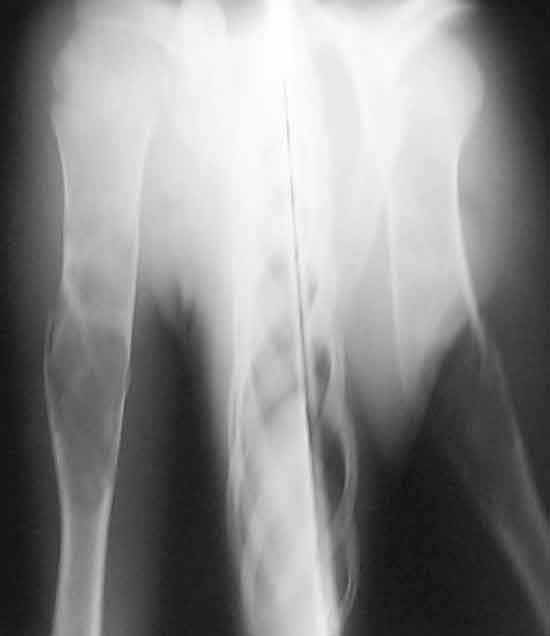

This 12 yr old boy was treated by me in May 2002 for pathological fracture right humerus conservatively. Curettage and bone grafting was suggested but parents were not willing. Xrays taken on 6th July 2002 shows the fracture united. He was protected by an Alkathin Brace for the Right Arm.

On 6th September 2003, he sustained refracture due to trivial trauma while he was not using the brace and X rays taken this time are also attached. Now that the lesion has migrated to the centre with growth and looks ?less in size compared to 2 years ago, should I advise curettage and bone grafting now? My clinical diagnosis is fibrous dyslasia. In case surgery is advised, do it immediately or wait for the fracture to get sticky.

6-9-03